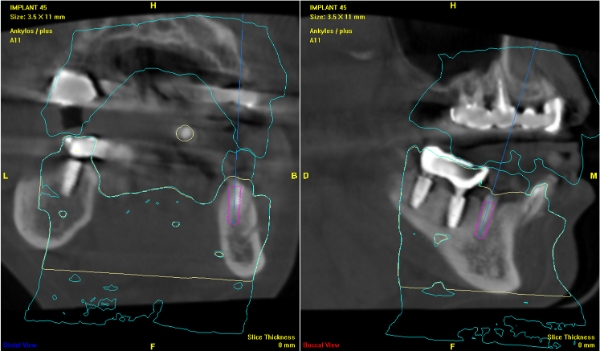

電腦斷層評估植牙位:#44

電腦斷層評估植牙位:#45